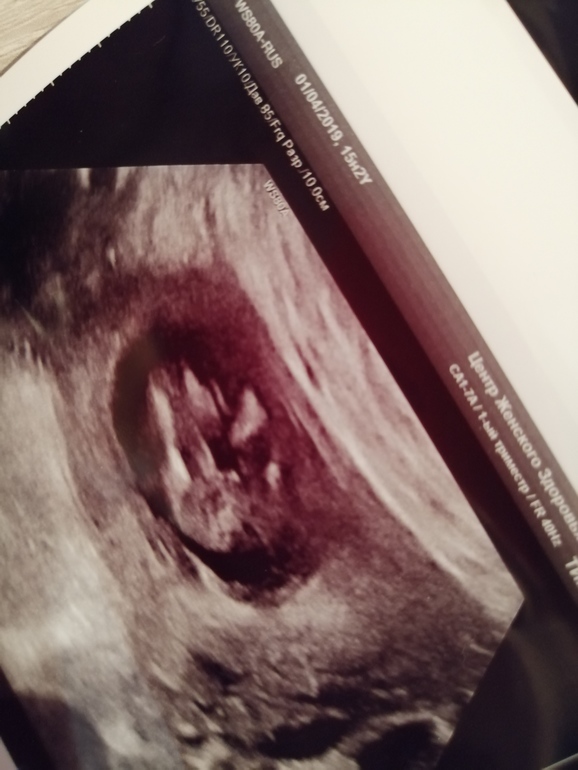

БеременностьЗнаю, многие уже видели наше фото с узи, но не могу успокоиться ся🤭Начинаю рассматривать и кажется, что чёт торчит🙄Хотя сколько фото девочек пересмотрела, вроде похоже.. 🤷♀️Поговорите со мной, если можно мамы девочек, которым пол определяли 14. 15недель,покажите своих девчушек... Прошу тапками не кидать, это уже не лечится 😪

Тут голову не видно😁

Фото под попкой сделано, 2 ножки и посерединке смотреть)))